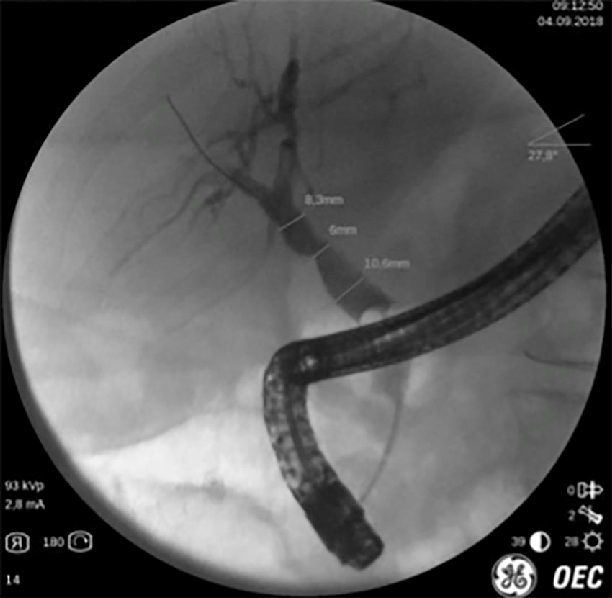

Q.46. A patient was diagnosed with obstructive jaundice. What is the best method to diagnose common bile duct obstruction?

Correct Answer : A

The best method to diagnose common bile duct obstruction is ERCP. It allows direct visualization of the bile duct and pancreas and can also be used to treat obstruction, such as removing stones.